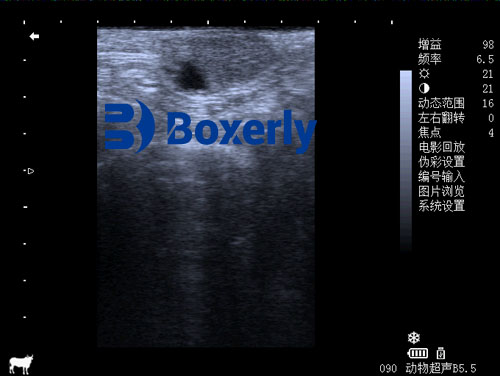

In traditional practices, pregnancy detection was done using manual rectal palpation—a technique that, while effective in skilled hands, lacks the clarity and specificity of modern imaging. Ultrasound has revolutionized this process by providing real-time, high-resolution imaging of the uterus and ovaries. With a transrectal probe, veterinarians can accurately determine whether a cow is pregnant as early as 25 to 30 days post-breeding.

This is where ultrasound proves invaluable. With a linear array transrectal probe, veterinarians can examine the structural integrity and physiological state of the uterus and ovaries. For example:

Endometritis appears as thickened uterine walls with fluid echoes.

Pyometra shows echogenic pus within the uterus.

Ovarian cysts and inactive ovaries can be visualized based on their size, shape, and internal consistency.